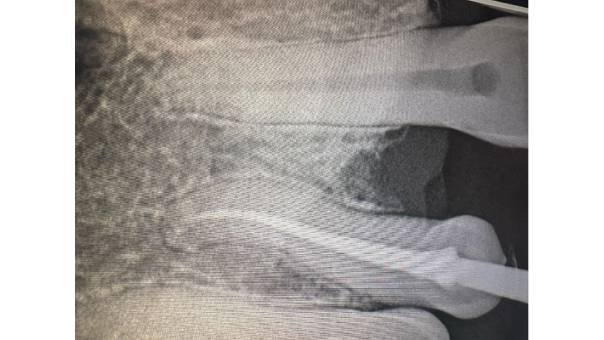

Radiograph after extraction of the mesioden

Radiographs after Rootcanal treatment

Extraction of the mesioden

Root canal treatment of the Upper Right Central and Lateral Incisors

Prosthetic rehabilitation with a permanent fixed bridge

To enhance both function and aesthetics, we utilized a creative restorative approach. The patient's peg lateral was reshaped to function as a canine, and the missing tooth was replaced as a Lateral Incisor—restoring symmetry and balance to her smile.